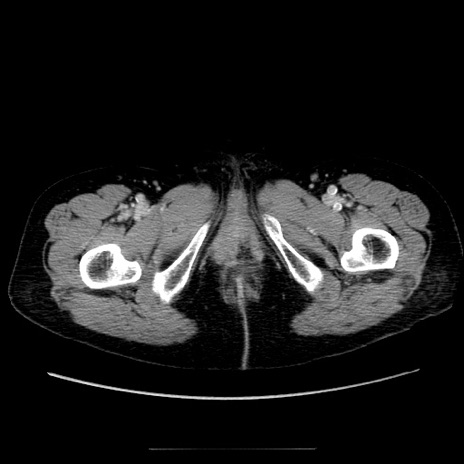

症例5(横断像)

【症例】70歳代女性

【主訴】お腹が張る

【現病歴】1週間くらい前から腹部膨満の自覚あり。昨日夜から増悪したため、本日救急外来受診。

【身体所見】意識清明、BT 36.5℃、BP 165/106mmHg、HR 80bpm、SpO2 98%、腹部:膨満、軟、自発痛・圧痛なし、触診にて不快感あり、腸蠕動音:減弱

【データ】WBC 12600、CRP 1.04